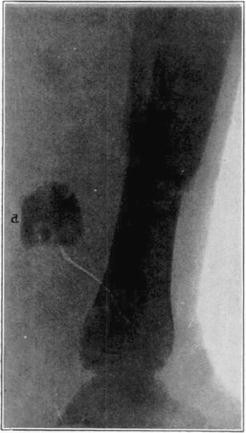

Case 4. Large splinter (a) displaced into soft parts from fresh fracture of tibia.

Case 4. The same (a) seven years later, showing reduction in size of splinter and apparent replacement by very spongy new bone.

Case 5. Tibial graft thirty-nine days after insertion in humerus.

Case 5. Ten years and eight months after operation. Shows non-functioning portion of graft in medullary cavity practically unchanged, but the functioning portion above hypertrophied and transformed.